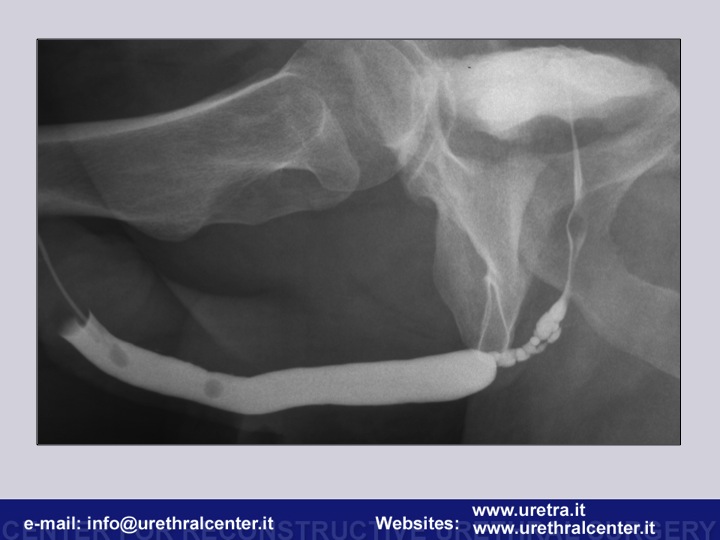

Early management in pelvic urethral injuries

What urethral stricture is and how we can make a diagnosis and arrange a surgical therapeutic strategy. An overwiev from the external urinary meatus to the bladder neck.